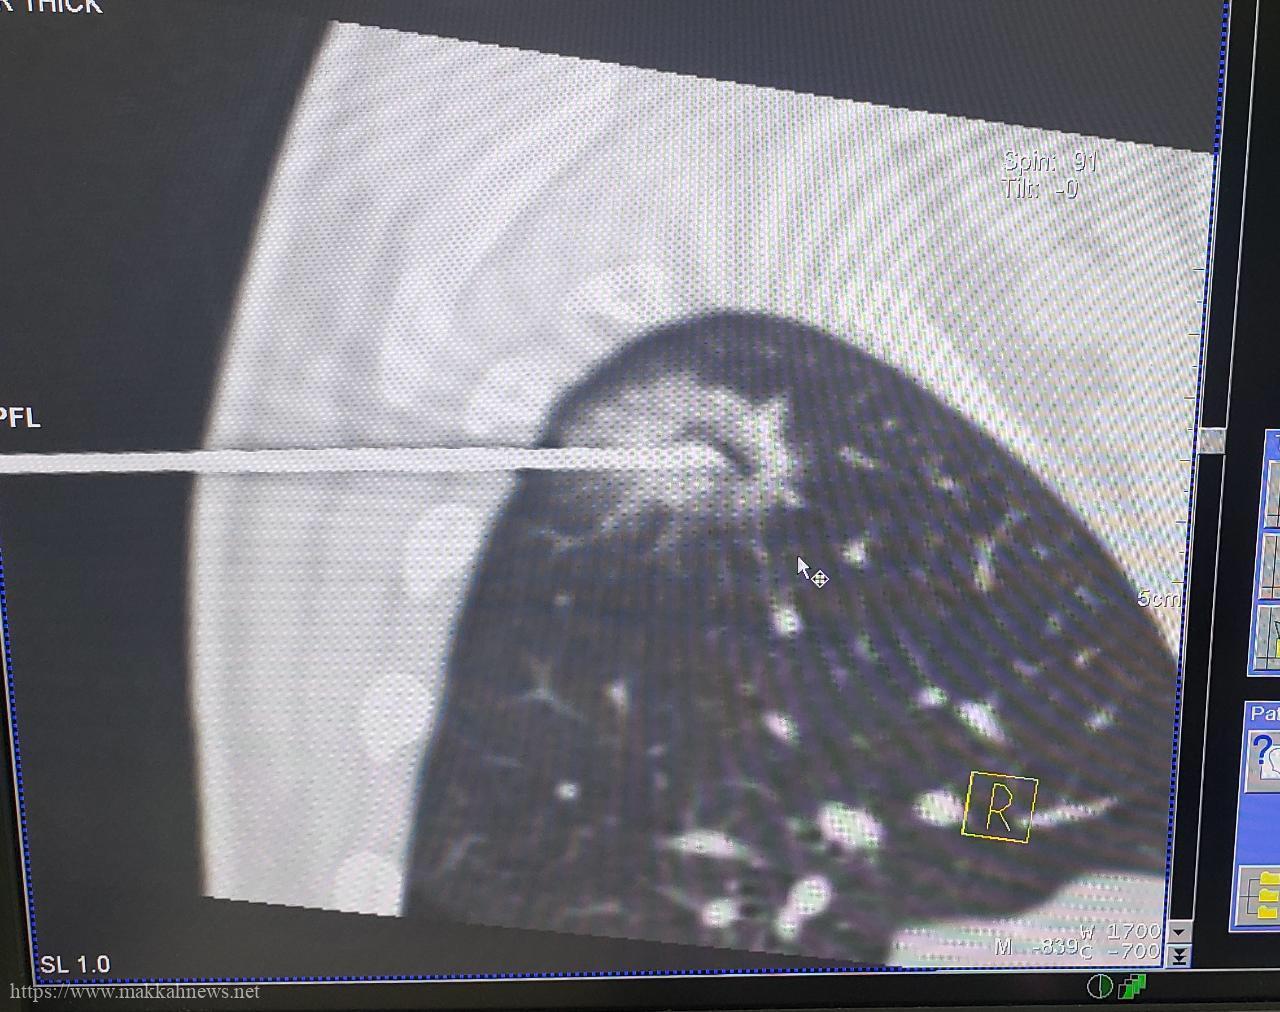

نجاح أول عملية بتقنية التبريد للقضاء على ورم لاربعيني بطبية مكه

مكة) – فوزية الفواز تمكن فريق طبي تخصصي بمدينة الملك عبدالله الطبية بالعاصمة المقدسة ممثلا بقسم الاشعة التداخلية من القضاء…